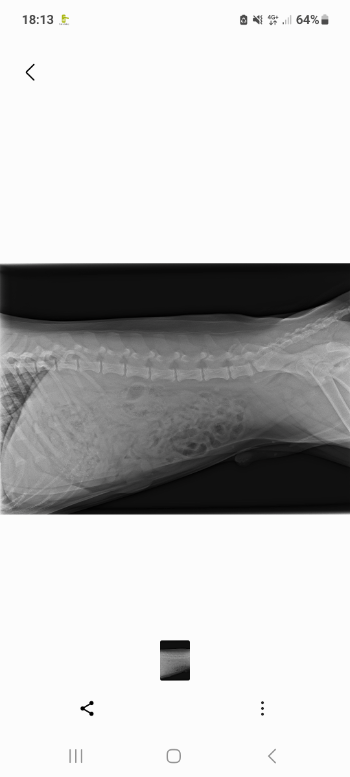

Het is een mogelijkheid om joey te opereren en dat wil zeggen heupkop verwijdering eerst 1 kant de.slechtse en half jaar later.de 2 kant

Dus vandaag met dierenarts besproken dat ik in het voorjaar hem.laat opereren kosten per heup ongeveer 500 euro met rongfoto is het dan 600 euro